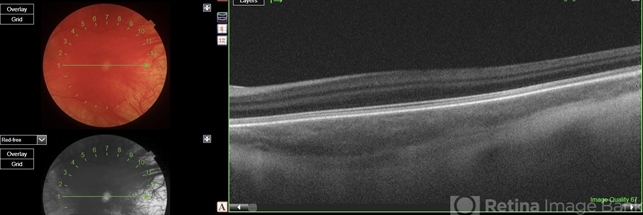

- oculocutaneous albinism

Scanning laser ophthalmoscope

Optos Daytona - Description

- OCT image of left eye showing foveal hypoplasia